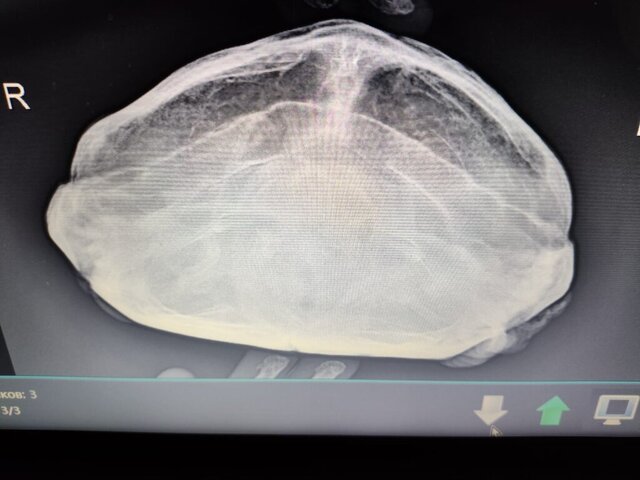

@moth Врач из этой клиники и ставил в задние, но не указанный. Для информации прилагаю рентген

IMG-20241223-WA0006.jpg

IMG-20241223-WA0005.jpg

IMG-20241223-WA0004.jpg

@Avdot я к сожалению снимок не могу прокомментировать, т.к. у вас случай тяжёлый и моих знаний тут не достаточно